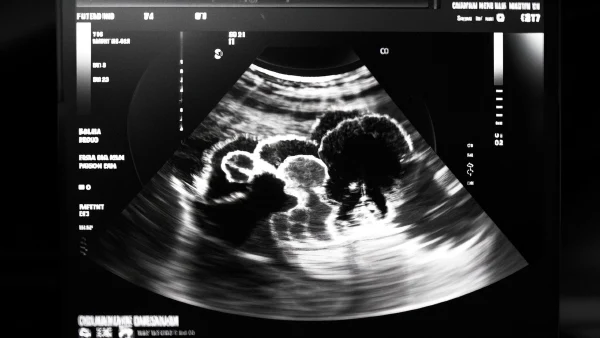

03 实性病变的超声特征

超声下,实性病变会呈现一定的“个性化”表现。但临床上,医生主要关注这几个方面:回声强度(反射亮不亮)、边界清晰程度、形态规则性以及内部结构。

04 如何通过超声鉴别不同类型实性病变?

临床上,很多实性病变需要超声帮助鉴别是肿瘤、结节还是其他。“实性”只是一个起点,下面用实际例子说明医生常关注的几个点。